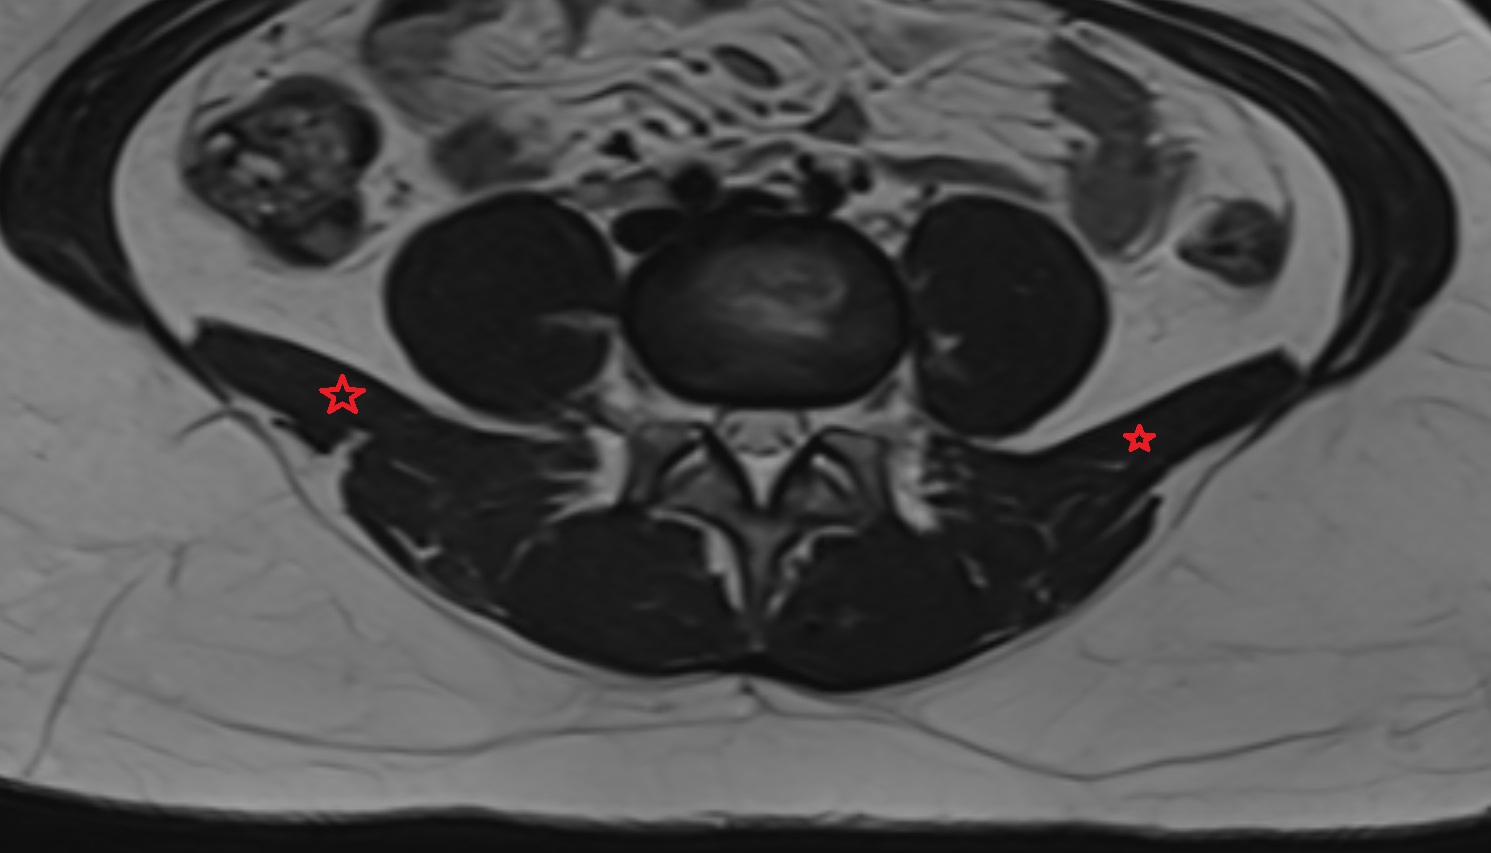

- Psoas major muscle

- Quadratus lumborum muscle

- Cauda equina